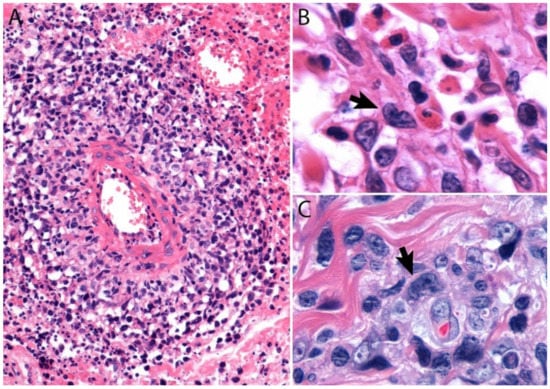

- Pandiar, D.; Smitha, T. The “hallmark” cells. J. Oral Maxillofac. Pathol. 2019, 23, 176–177. [Google Scholar] [CrossRef]